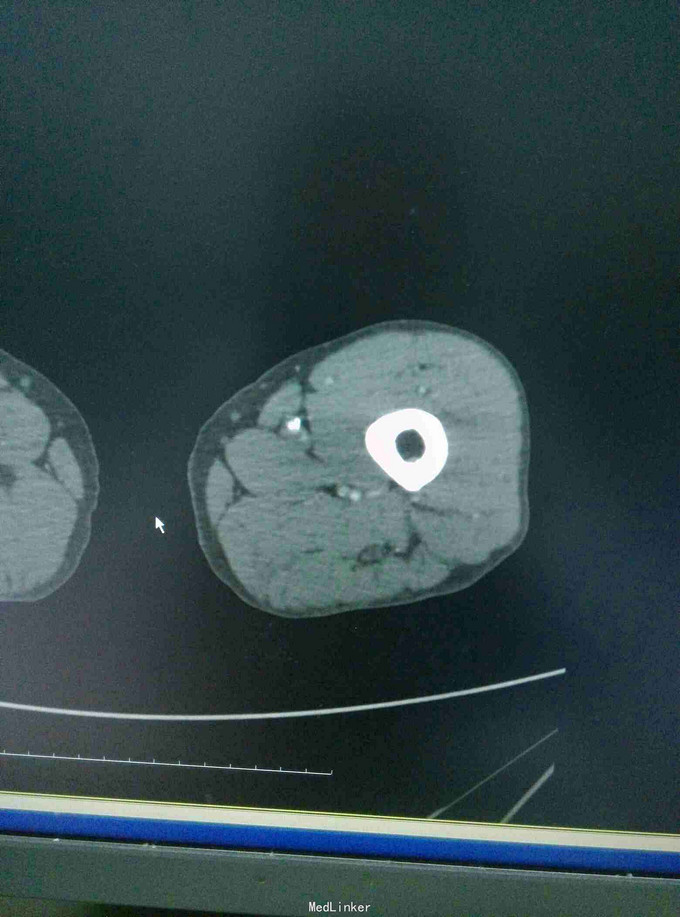

左下肢皮温降低,左足背可见紫红色淤斑,左股动脉扪及微弱波动。下肢血管成像提示:双下肢动脉节段性不同程度狭窄、闭塞。

双下肢动脉硬化闭塞症 手术:左侧髂动脉探查术,术中探查股动脉,导丝导管尝试通过闭塞段髂动脉,但反复尝试无法继续。右侧也无法通过。家属放弃。

ASO是动脉粥样硬化引起的,好发于45岁以上男性,早期主要表现为间歇性跛行,晚起出现静息痛、缺血坏跙或溃疡。动脉造影有助于确定诊断,临床上可采用PTA,内膜剥脱术、旁路转流术等。